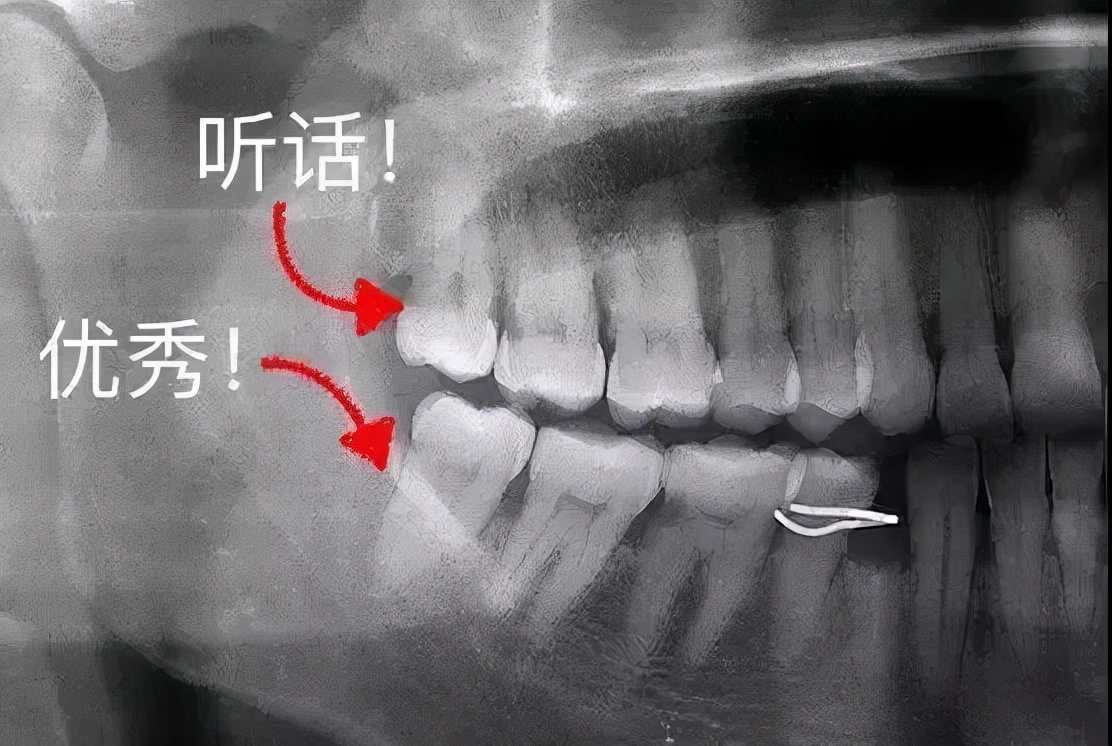

箭头所示处为盲袋,容易积存食物碎屑和细菌

来源:Wikipedia

◎ 邻牙的瘟神

本来就没有地儿了,智齿偏要长,还胡乱窜,最惨的是智齿的“邻居”,真是太难了,轻则牙齿表面生成菌斑,重则整个牙为智齿“陪葬”。智齿甚至能把整副牙都挤歪。